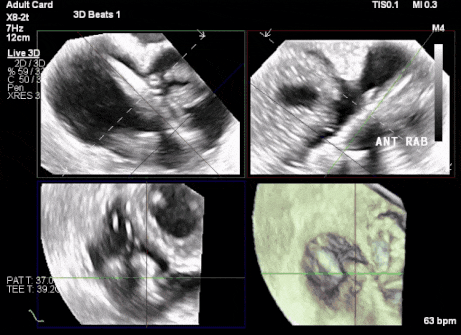

術中DSA顯示起搏器導線的干擾,右心室造影確定瓣環位置,操作空間小

術后超聲顯示人工瓣膜穩定性良好,瓣葉啟閉正常

術前超聲顯示三尖瓣重度反流合并拴系

術中TEE成像困難,偽影干擾